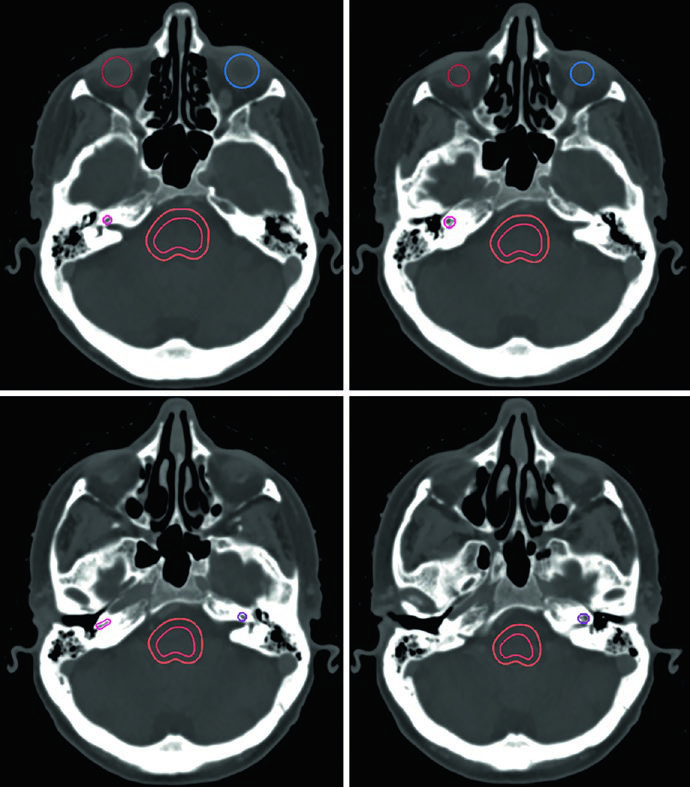

Tumores glômicos são neoplasias neuroendócrinas raras que podem ocorrer na base do crânio, cabeça e pescoço, tórax e abdômen, nomeados conforme o sítio de origem. As opções terapêuticas incluem embolização, ressecção e radioterapia, com altas taxas de controle local. A avaliação detalhada por RM e TC é indispensável para detectar invasão da cavidade timpânica, forame jugular, região petroclival, seio cavernoso ou canal do hipoglosso. A TC em janela óssea complementa a RM ao revelar erosão óssea.

A Figura 29.14 mostra um tumor glômico carotídeo que separa as artérias carótidas interna e externa. O GTV (vermelho) foi delineado em RM T2 SPACE co-registrada à TC, com expansão de 3 mm para PTV. O paciente recebeu 25 Gy em 5 frações com linhas de isodose de prescrição (25 Gy), 110% (27,5 Gy), 80% (20 Gy) e 50% (12,5 Gy), com preservação de parótidas, glândulas submandibulares, cavidade oral e parede orofaríngea.

O caso da Figura 29.15 demonstra um cenário mais complexo: tumor glômico recorrente no bulbo jugular esquerdo após embolização e ressecção, tratado com 54 Gy em 30 frações. O GTV foi gerado co-registrando imagens de RM do diagnóstico inicial e da recorrência, incluindo a extensão original da doença, alterações pós-operatórias, leito tumoral e doença recorrente com cobertura até a base do crânio. Margem de 0,3 cm definiu o PTV. Múltiplos OARs — tronco encefálico, mandíbula, parótidas, medula com PRV, parede orofaríngea, cavidade oral e lábios — foram cuidadosamente delineados.